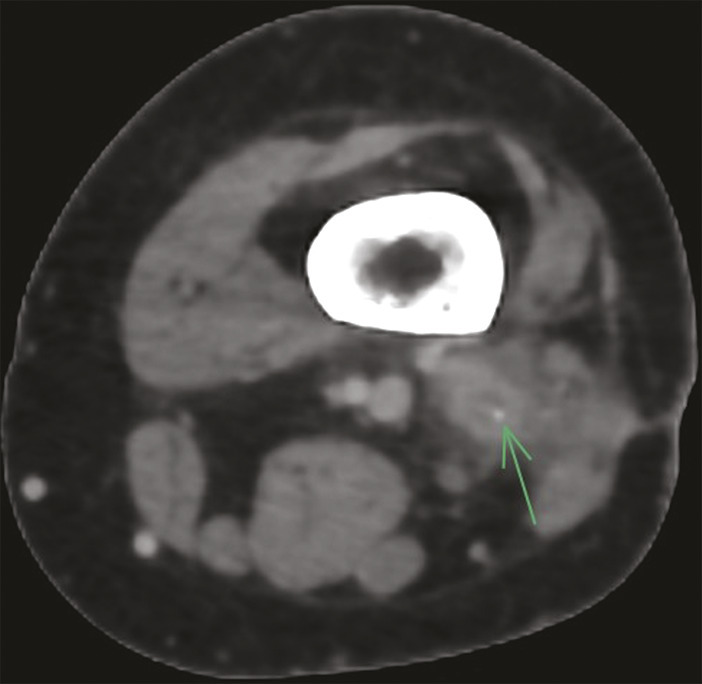

Une radiographie standard complétée par un scanner (fig. 1 ) met en évidence un épaississement cortico-périosté de la diaphyse fémorale, une condensation de l’os médullaire centrée par une ostéolyse linéaire décrivant un trajet fistuleux qui alimente une collection abcédée des parties molles renfermant des séquestres osseux (fig. 2 ). Le diagnostic d’ostéomyélite chronique est retenu.

L’imagerie radiologique standard montre un remodelage de l’os avec un épaississement cortical composé d’appositions périostées épaisses et irrégulières. Au sein de l’os, on observe des plages radiotransparentes dans lesquelles on peut retrouver un séquestre osseux. Le scanner et l’imagerie par résonance magnétique (IRM) permettent d’apprécier avec davantage de précision l’étendue de la maladie dans les tissus mous et la cavité médullaire, et représentent actuellement les examens de choix. Le scanner permet en particulier l’évaluation du cortex osseux, la recherche d’un séquestre osseux, un corps étranger ou une fistule. L’IRM permet de mieux apprécier les abcès ou collections.1,2